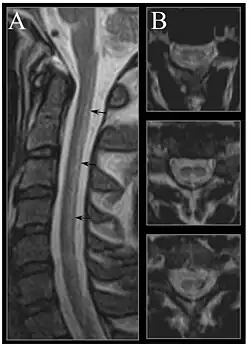

Zwyrodnienie powrózkowe rdzenia kręgowego

Zwyrodnienie powrózkowe rdzenia kręgowego (choroba Lichtheima, podostre złożone zwyrodnienie rdzenia kręgowego, ang. subacute combined degeneration of spinal cord, łac. myelosis funicularis) – zespół objawów neurologicznych spowodowanych uszkodzeniem sznurów tylnych i sznurów bocznych rdzenia kręgowego. Zazwyczaj występuje w przebiegu choroby Addissona-Biermera. Suplementacja witaminy B12 daje w tym przypadku całkowite wycofanie się objawów.

Na symptomatologię zespołu składają się objawy piramidowe: porażenie kurczowe, wygórowane odruchy głębokie, dodatni objaw Babińskiego; brak niektórych odruchów głębokich; osłabienie czucia powierzchniowego i głębokiego; zaburzenia koordynacji ruchów; ataksja[1].